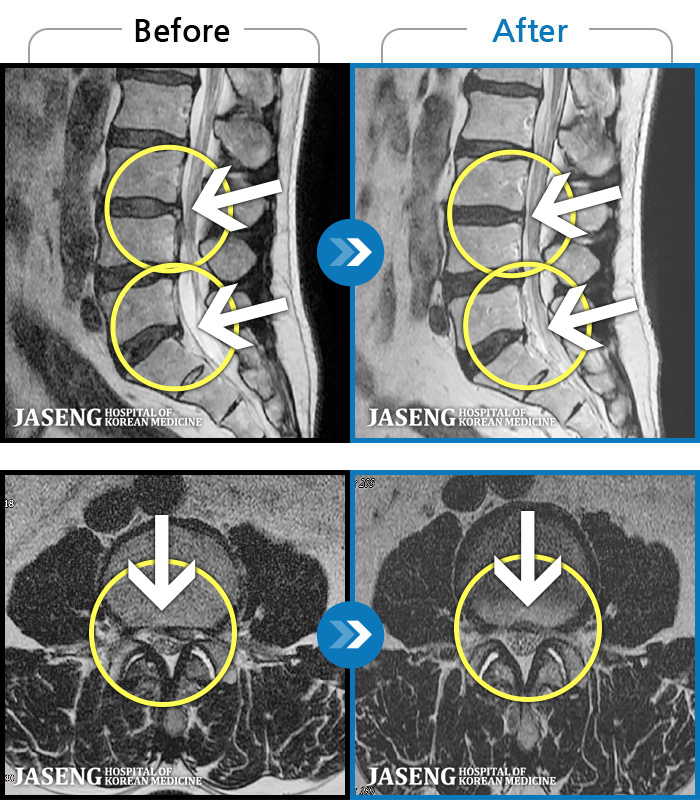

[ؿ] 24.10.10~25.04.23

ȯںп Ǹ ǿ ԿǾ, ο ġ ۿ Ƿ ġḦ Ͻñ ٶϴ.